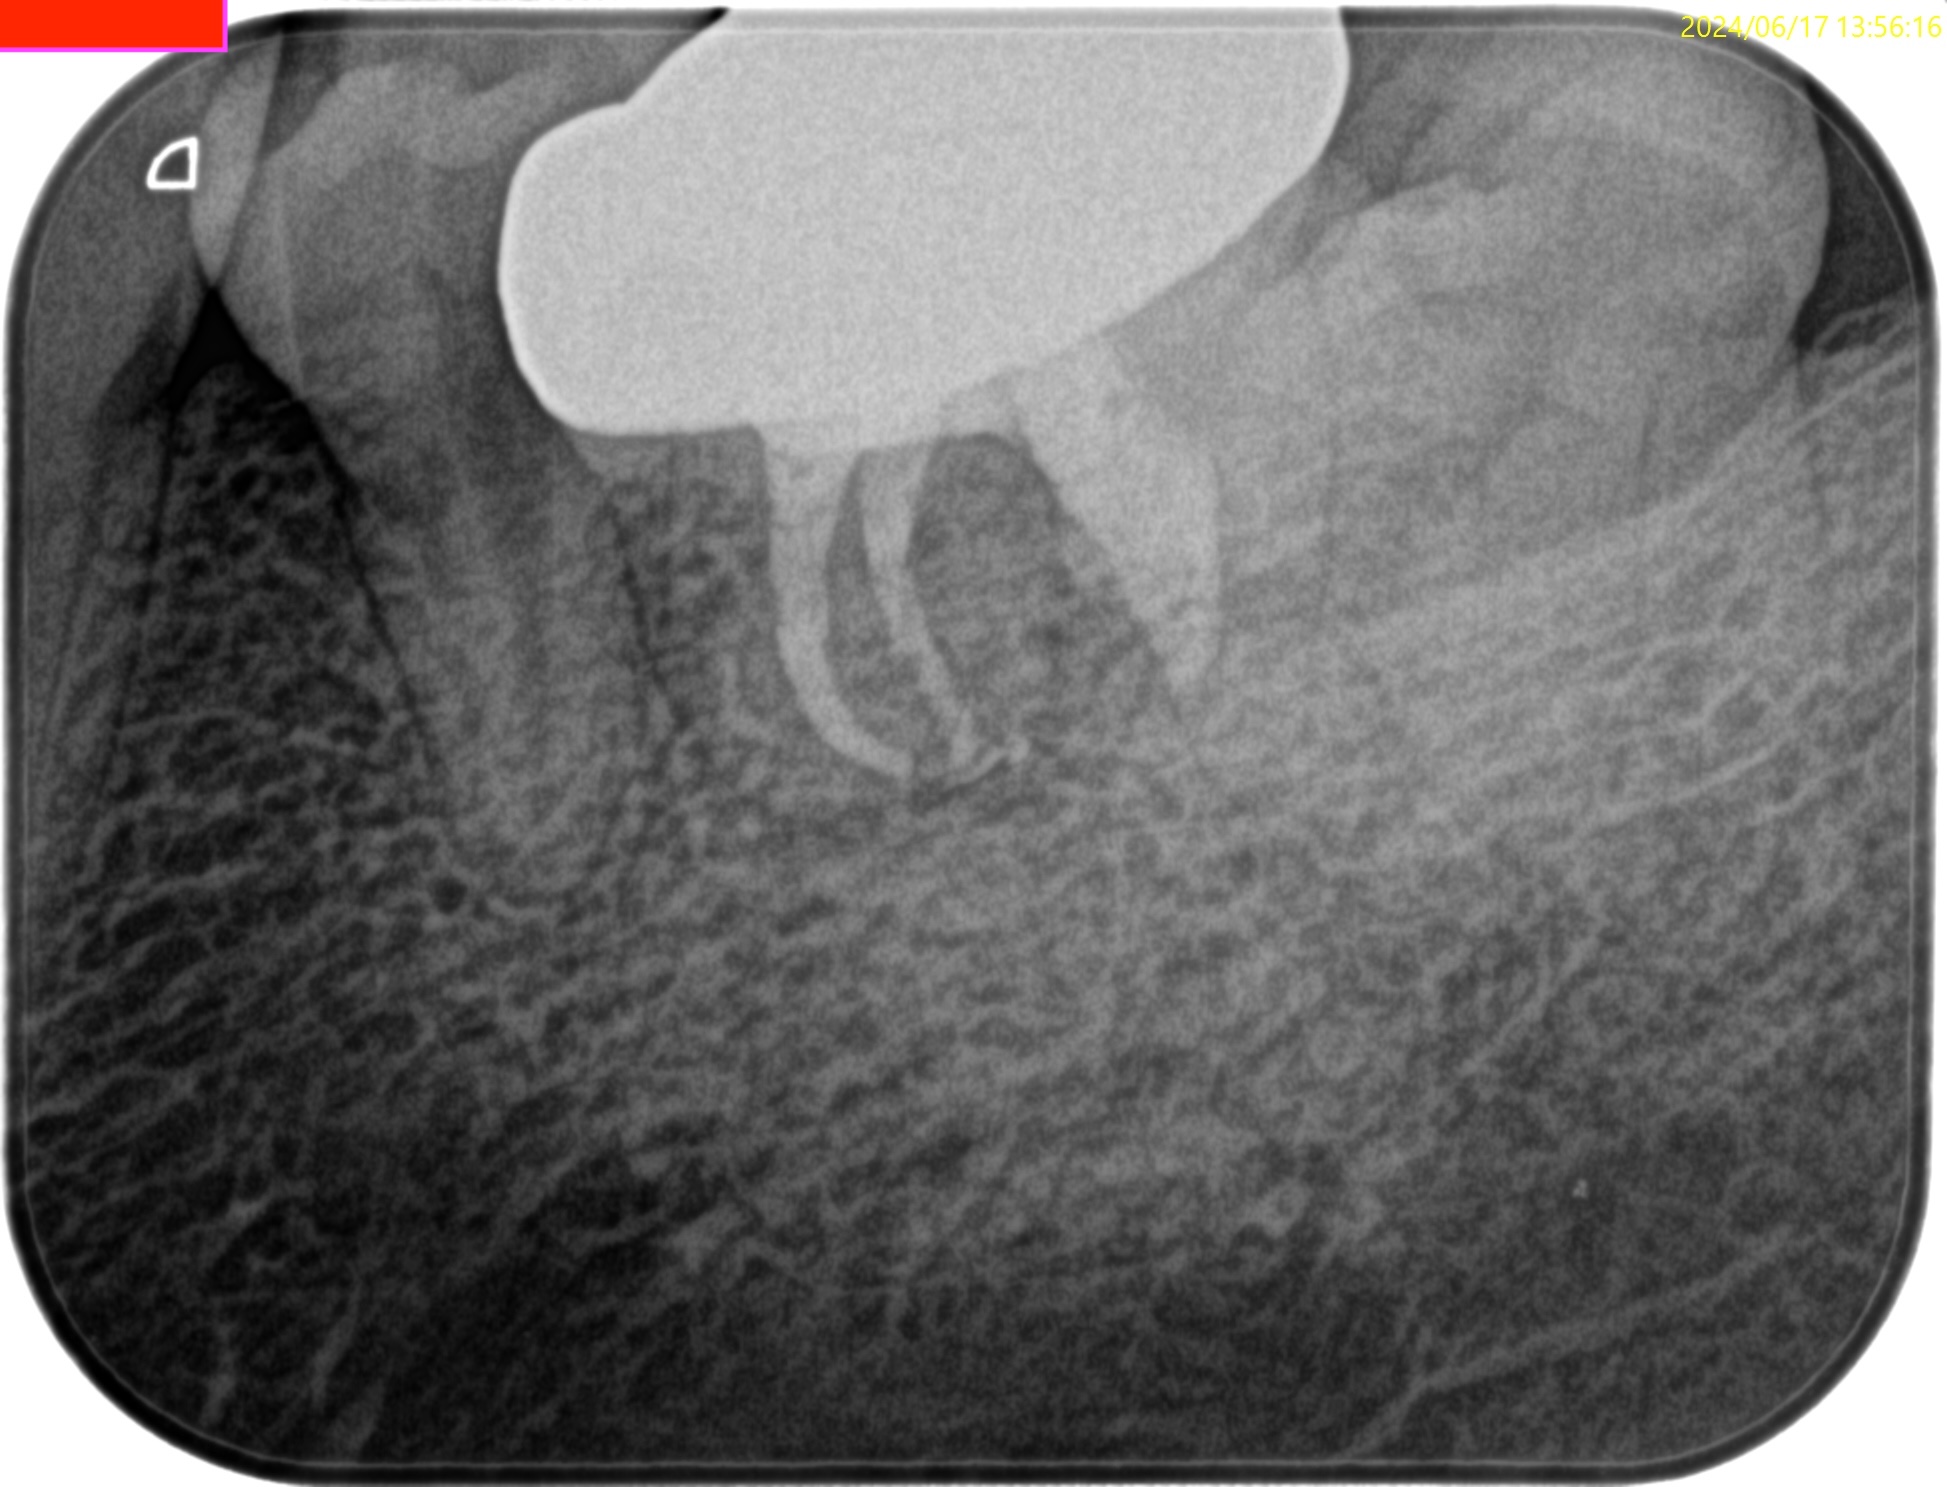

再根管治療に見込みはないため、Apicoectomyなのだが

当該部位を2mm Osteotomyすると#19 MのApexが発見できそこを3mm切断するには頬舌径が6.2mm必要である。

難易度は中だろう。

当該部位をOsteotomyした。歯槽骨は2mm削合する必要がある。

Apexを3mm削除し取り除いた。

逆根管形成はMB-MLを往復しなければならないが、

間がかなり離れているので逆根管形成には時間がかかる。

逆根管充填するが、その際はペントロンジャパンのエンドセム MTA クイックペースト Rで逆根管充填することにした。

術後にPA, CBCTを撮影した。

問題はないだろう。